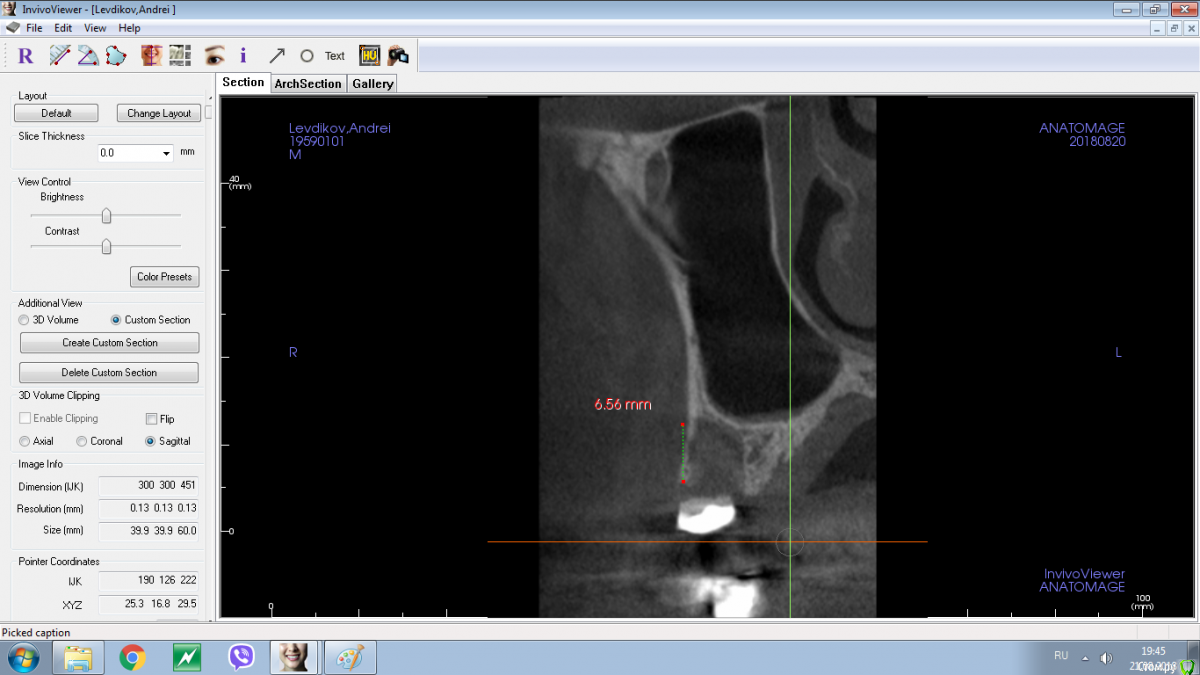

колесников Опубликовано 13 марта, 2019 Поделиться Опубликовано 13 марта, 2019 В первой лунке имплант ,второй корень подготовлен под удаление. Для консервации используйте графт это минимизирует атрофию кости,дефицит мягких тканей случится в любом случае,на момент имплантации понадобится сст. Ссылка на комментарий